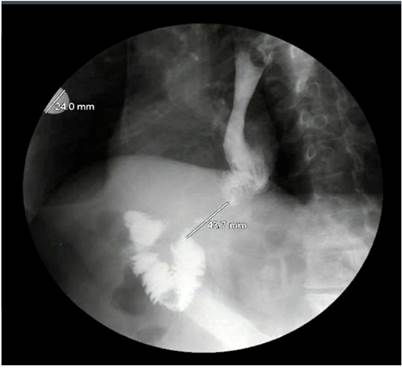

Como consecuencia de dichos hallazgos, se realizó una radiografía de las vías digestivas (Figura 3) y se evidenció una estenosis de 43 mm de íleon, distal a la anastomosis, lo cual sugirió la posibilidad de una recaída tumoral. Por tanto, se efectuó una tomografía computarizada (TC) de abdomen, en la que se observaron cambios posquirúrgicos de la gastrectomía total, la reconstrucción en Y de Roux y el engrosamiento de la pared intestinal en los sitios de anastomosis esofagoyeyunal y yeyuno-yeyunal, sin signos de obstrucción intestinal.